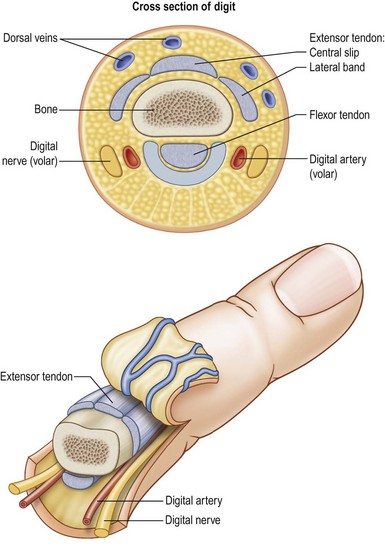

Hand Diseases and Surgeries

Expert management of hand conditions including trauma, deformities, nerve compression, and infections. Our surgeries focus on precision, function, and rapid recovery. Restoring hand strength and dexterity is our goal.

Tendon & Nerve Repair and Grafts

ASpecialized repair of injured tendons and nerves to restore movement and sensation. Microsurgical techniques ensure accurate alignment and healing. Early surgery improves functional recovery.

Microsurgery

High-precision microsurgical procedures allow reconstruction of nerves, vessels, and tissues under magnification. This enables limb salvage, complex reconstructions, and superior functional recovery. Executed with state-of-the-art technology.

Re-implantation

We specialize in emergency re-implantation of amputated fingers and limbs. Using microsurgical expertise, we aim to restore circulation, function, and appearance. Early intervention is key to successful outcomes.